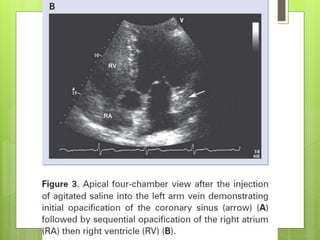

Figure 1. Transesophageal echocardiography revealed both atrial and right ventricular

enlargement (left), a defect of the partial coronary sinus (middle), and shunt of the left atrium

to the dilated coronary sinus (right) at the near longitudinal plane.

Huang X Circulation 2007;116:e373-e373